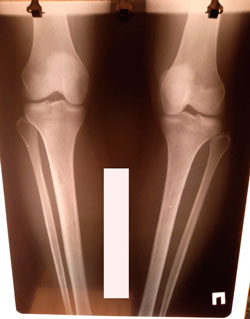

Исходник - 29 лет.

Дата операции - 12.02.2021

перед крутками

на фиксации